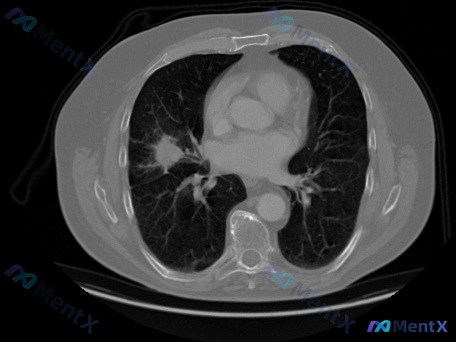

整理到一份胸部CT肺窗横断面的影像分析资料,先不放临床背景,只看影像特征,大家第一眼的鉴别思路会怎么排? 核心影像表现: - 病灶位置:严格局限于双肺下叶背侧近后胸壁处(坠积部位),双侧对称 - 密度:以实性为主,伴部分磨玻璃样改变 - 边缘:模糊,与正常肺组织界限不清 - 其他:未见明确结节、空洞...

整理到一份胸部CT的肺窗图像资料,先不看临床背景,只看影像表现: - 双肺下叶背侧大范围密度增高影,胸膜下分布为主,有双侧对称性 - 磨玻璃影(GGO)与局灶性实变影混合,可见支气管充气征 - 病变边缘有细小网格状纹理,未见明显蜂窝肺或空洞 - 肺门血管影形态尚可,双侧胸膜未见明显积液或增厚 之前可...